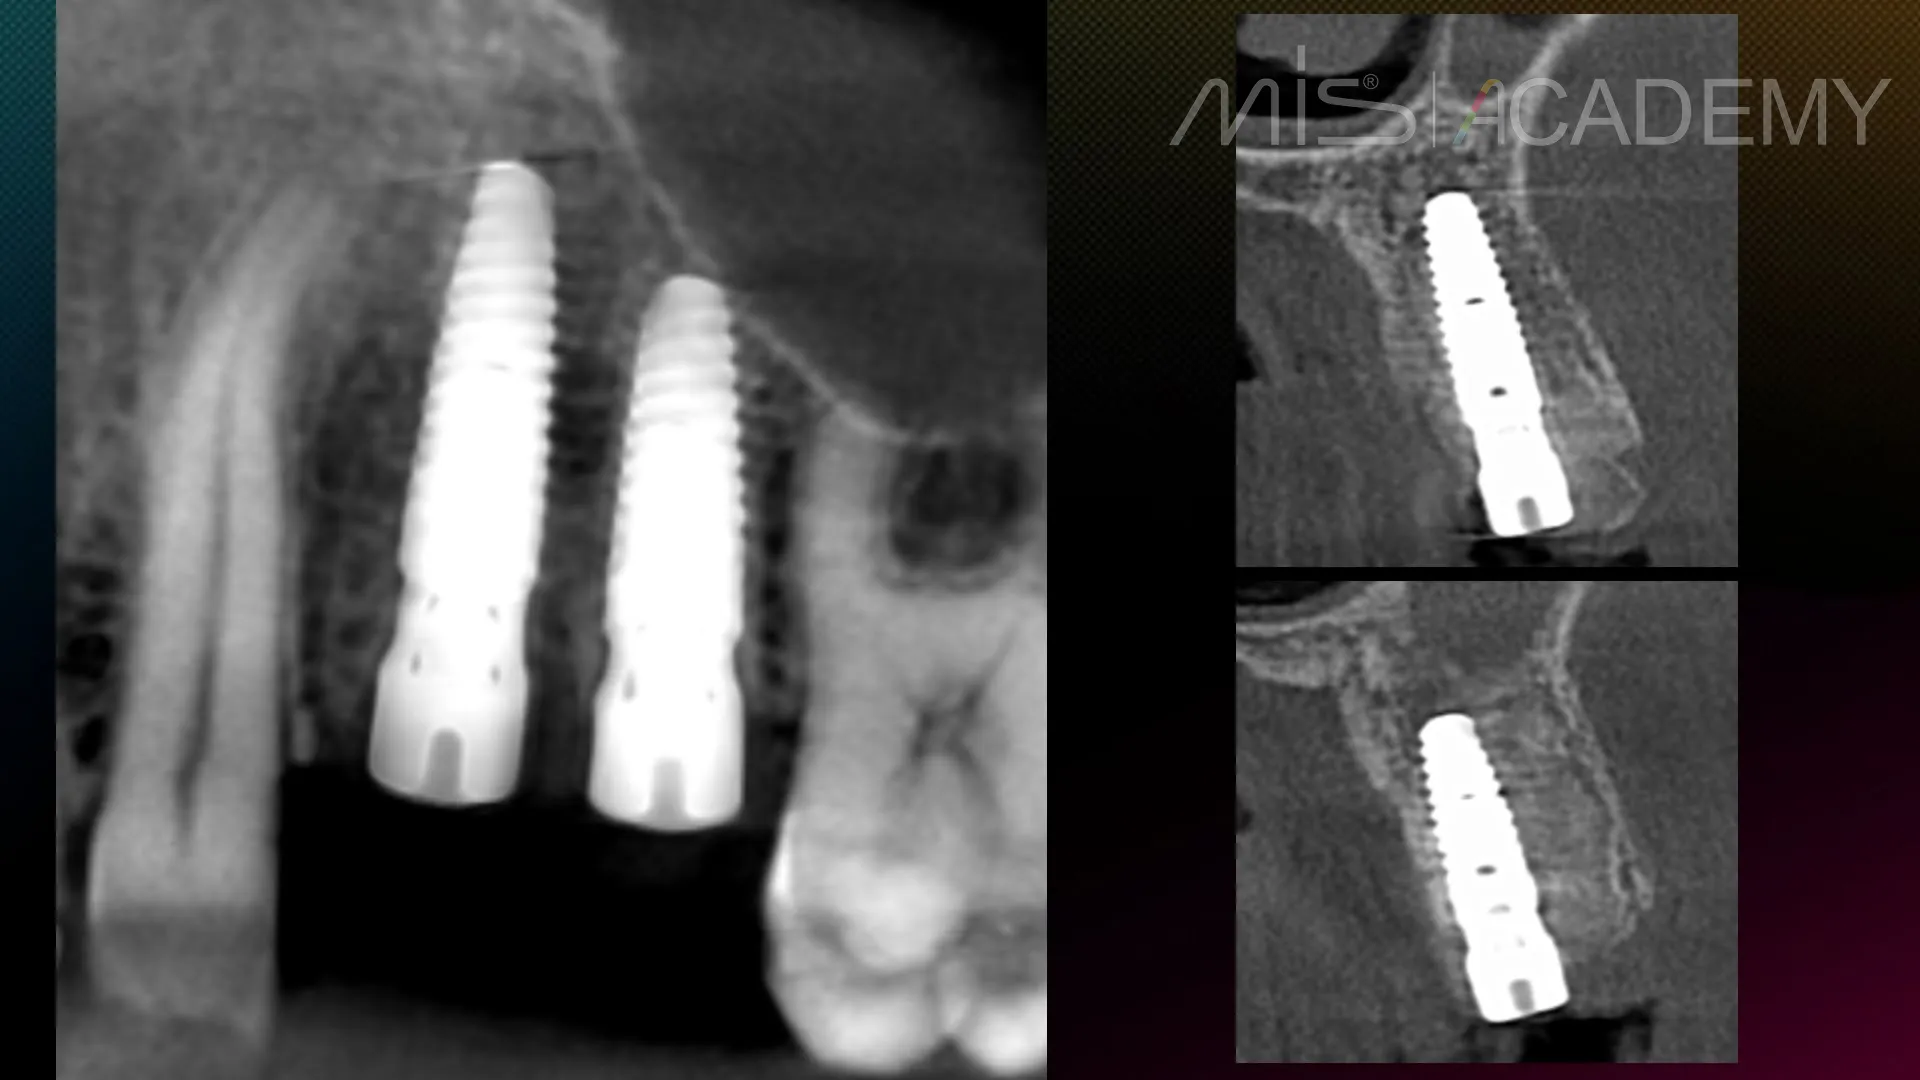

— Установка имплантатов MIS C1.

— CONNECT абатменты.

— Bio-oss, стимул-осс.